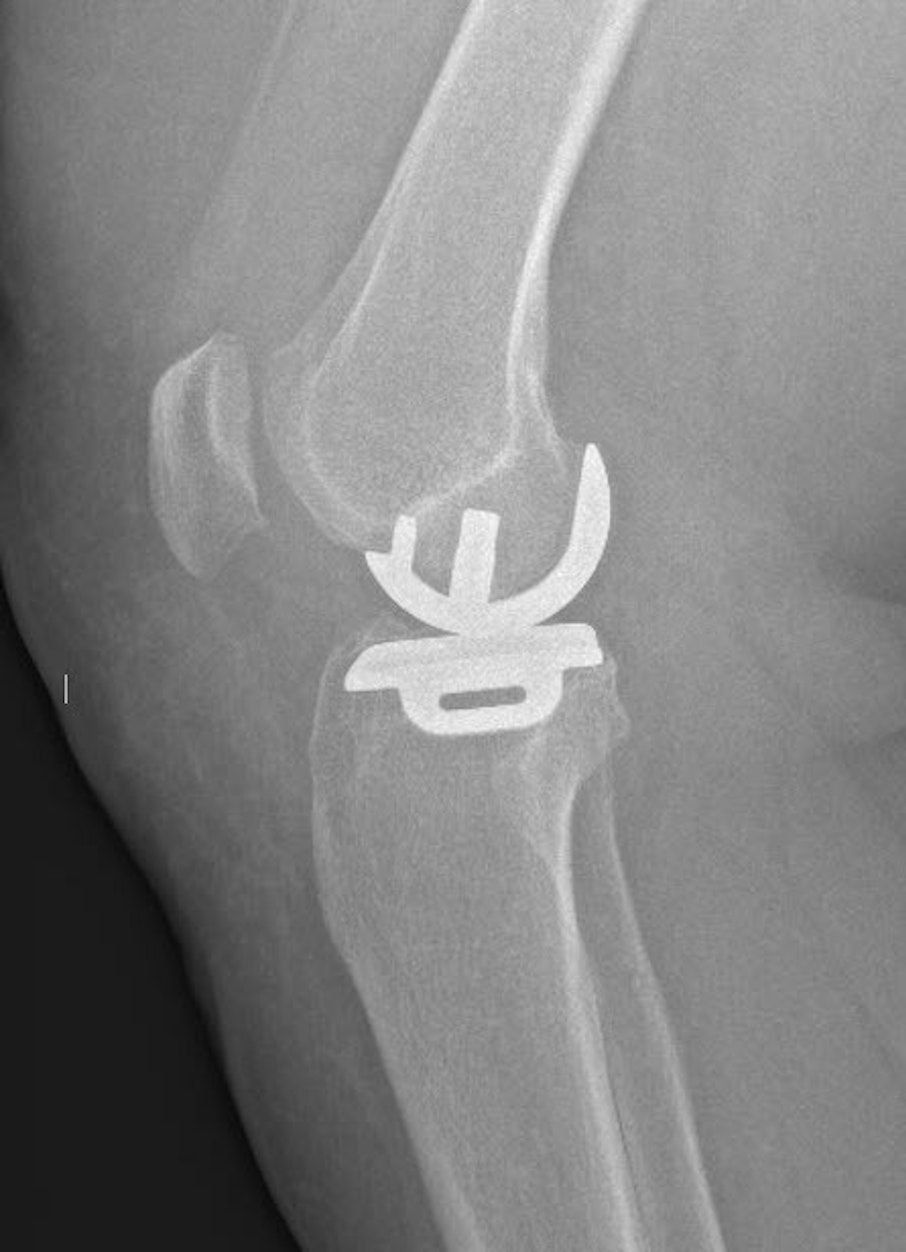

Bij een unicompartimentele knieprothese (UKP) - halve knieprothese in de volksmond - vervangen we enkel het versleten gewrichtscompartiment.

De prothese bestaat uit 3 componenten: een bolvormige component die op het dijbeen wordt geplaatst en een vlakke component die op het dragend deel van het scheenbeen wordt geplaatst. Daartussen zit een mobiele component die de functie van de meniscus overneemt.

De componenten die gefixeerd worden op het dijbeen en op het scheenbeen bestaan uit een Chroom Kobalt Molybdenum legering. Daartussen zit een mobiel polyethyleen component dat gemaakt is uit ultra high moleculair weight polyethylene (UHMWPE).

Er zijn twee methoden om de componenten te fixeren: met botcement of cementloos. In de meeste gevallen gebruiken we de cementloze techniek. Bij de cementloze techniek groeit het bot van de patiënt in een speciale hydroxie-apatiet laag van de prothesecomponenten in. De keuze tussen de twee technieken hangt onder andere af van de botkwaliteit van de patiënt. Bij heel kleine patiënten of bij zwakke botkwaliteit fixeren we de prothese doorgaans mét cement.